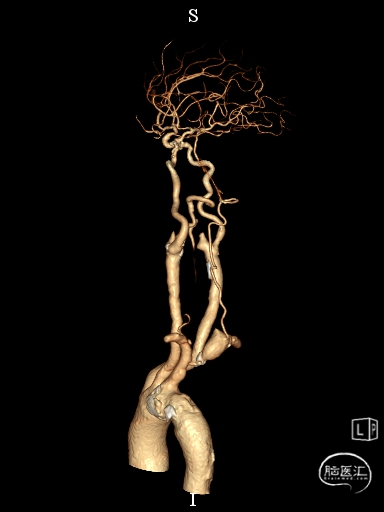

CTA提示:右侧椎动脉纤细,左侧椎动脉V1、V4段纤细。

术前DSA影像

右侧颈内动脉起始部中度狭窄,未见血流向后循环代偿。

左侧颈内动脉造影提示后交通开放,代偿供应后循环。

左侧椎动脉开口重度狭窄,前向血流缓慢,V4闭塞。